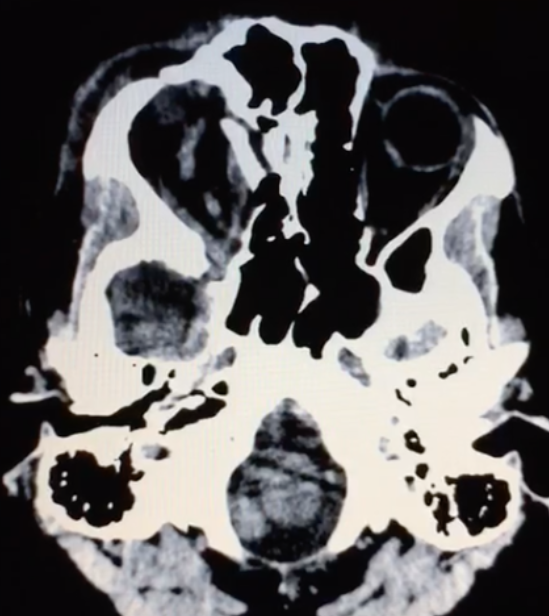

- Tomografia de crânio estrutura captante com a invasão de contraste. Ausência de coleção purulenta e presença de lesão em topografia de seio cavernoso e evidência da veia oftálmica superior. Além disso, a TC mostra sinais de traumatismo prévio (fratura frontal).

As fístulas arteriovenosas (FAVs) da região do seio cavernoso (SC) são lesões raras e difíceis de diagnosticar. Os principais sinais e sintomas são proptose, hiperemia conjuntival, quemose, paralisia dos III, IV, V e VI nervos cranianos, ptose palpebral, glaucoma, redução da acuidade visual e cefaleia. Nas fístulas carótido-cavernosa existe um defeito na parede da artéria carótida interna (ACI) que a comunica diretamente com o SC e, em consequência, um shunt arteriovenoso de grande volume. Na TC podemos identificar dilatação ou trombose da veia oftálmica superior (VOS), proptose, contrastação precoce do SC, espessamento da musculatura extraocular e edema da gordura periorbitária3.

As FCC diretas apresentam na maioria dos casos um alto débito ao contrário das FCC indiretas que em termos hemodinâmicos são de baixo débito. Etiologicamente as primeiras são traumáticas em cerca de 75% dos casos podendo, no entanto, ocorrer espontaneamente. As FCC indiretas são geralmente espontâneas, ocorrendo classicamente em mulheres pós-menopáusicas ou em grávidas. O diagnóstico é efetuado pela clínica e por Tomografia Computadorizada de crânio e/ou Ressonância Magnética Nuclear das Órbitas, onde o sinal mais específico é a dilatação da veia oftálmica superior. No entanto, o diagnóstico definitivo, a caracterização da fístula e o planejamento do tratamento endovascular só são possíveis com a angiografia cerebral6.